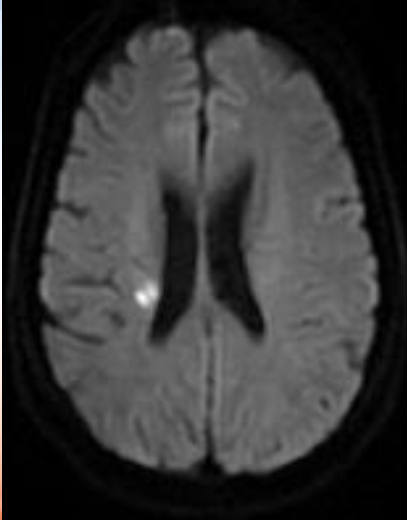

影像诊断

颅脑DWI

病历夹什么径技·第152期|串联营病历夹:川陕大营_https://www.jmylbn.com_新闻资讯_第40张

病历夹什么径技·第152期|串联营病历夹:川陕大营_https://www.jmylbn.com_新闻资讯_第41张

<<滑动查看下一张图片>>

诊断:右侧放射冠区急性脑梗死。